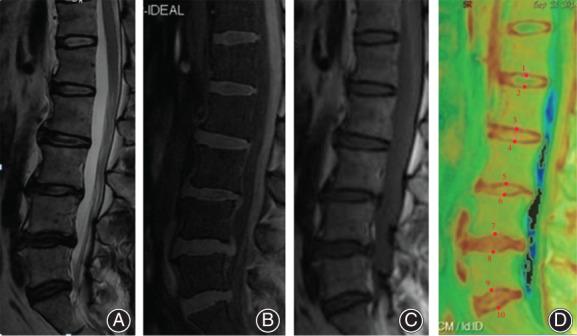

The T2 value of lumbar cartilage endplates was measured using the T2 mapping imaging technique, aiming to explore the correlation between the T2 value and Pfirrmann grading of intervertebral discs.

METHODS

A total of 130 patients with lumbar spine MR examination due to persistent low back pain were enrolled, including 71 men and 59 women (age: 21-63 years). Lumbar Modic changes and Schmorl nodules were recognized by conventional T1WI and T2WI images in 49 patients, and these patients were excluded from the study. A total of 81 patients were enrolled in this study, including 45 men (45.16 ± 12.20 years) and 36 women (43.33 ± 11.27 years). Pfirrmann (Pm) grading of each lumbar disc was performed based on conventional T2WI median sagittal images and the position of cartilage endplates (CEP) was determined by IDEAL-SPGR images. Meanwhile, the T2 mapping technique was used to obtain T2 values of cartilage endplates. The T2 values of CEP corresponding to different Pm grade discs were compared, and the correlation between the T2 value and the Pm grade of intervertebral discs was analyzed.

RESULTS

The T2 values of cephalic and caudal CEP of L in Pm grades I-II, Pm grades III, and Pm grades IV-V were 61.96 ± 5.89 ms, 54.45 ± 3.29 ms, 42.47 ± 3.69 ms and 64.35 ± 5.93 ms, 55.28 ± 3.97 ms, 44.75 ± 2.12 ms, respectively. For cephalic and caudal CEP of L , the T2 values in Pm grades I-II, Pm grades III, and Pm grades IV-V were 62.96 ± 6.93 ms, 55.19 ± 4.02 ms, 48.67 ± 4.56 ms and 65.51 ± 6.49 ms, 57.16 ± 5.55 ms, 52.05 ± 4.20 ms, respectively. The T2 values of cephalic and caudal CEP from L to L -S in Pm grades I-II, Pm grades III, and Pm grades IV-V were (63.72 ± 5.76 ms, 53.96 ± 6.52 ms, 48.05 ± 5.00 ms), (65.46 ± 6.37 ms, 55.70 ± 7.50 ms, 48.10 ± 3.27 ms); (66.34 ± 7.68 ms, 56.76 ± 9.48 ms, 47.80 ± 4.33 ms), (64.44 ± 4.65 ms, 59.30 ± 8.80 ms, 47.30 ± 5.78 ms), (65.32 ± 5.11 ms, 55.33 ± 6.65 ms, 48.18 ± 5.37 ms), and (63.47 ± 4.92 ms, 50.32 ± 8.86 ms, 44.77 ± 4.69 ms), respectively. There were significant differences in T2 values of cartilage endplates between the Pm grades I-II, III, and IV-V of intervertebral discs (P = 0.000). T2 values corresponding to Pm I-II grades were higher than those in Pm III grade, while T2 values in Pm grades IV-V were lowest. The T2 value of the L , L -S segment endplates was highly correlated with the Pm grades (r = -0.711, -0.721, -0.796, -0.745; P = 0.000) and that of L , L endplates were moderately correlated (r = -0.542, -0.562, -0.637, -0.612; P = 0.000).

CONCLUSION

The T2 values of cartilage endplates revealed varying degrees of degeneration of intervertebral discs, and more severe degeneration corresponded to lower T2 values. Measurement of changes in the T2 value through cartilage endplates can be useful for the diagnosis of early intervertebral disc degeneration and the prevention of disc degeneration.